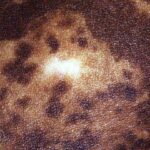

Trichrome vitiligo is characterized by both depigmented and hypopigmented macules in addition to normally pigmented skin. The natural evolution of the hypopigmented areas is progression to full depigmentation. Quadrichrome vitiligo refers to the additional presence of marginal or perifollicular hyperpigmentation. This variant is recognized more frequently in darker skin types, particularly in areas of repigmentation. Cases of pentachrome vitiligo have also been reported with additionally blue-gray hyperpigmented macules, representing areas of melanin incontinence (dermal melanin). Occasionally, patients with vitiligo may present with an unusual variant called the confetti type or vitiligo ponctue. These patients have several tiny, discrete hypomelanotic macules. Inflammatory vitiligo is characterized clinically by erythema at the margins of vitiligo macules.